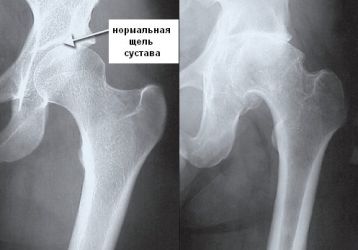

Массаж при коксартрозе тазобедренного сустава: правила выполнения, противопоказания, самомассаж

Помогает ли массаж при коксартрозе тазобедренного сустава, особенности проведения, показания к применению. Правила проведения сеанса и особенности самомассажа при коксартрозе.